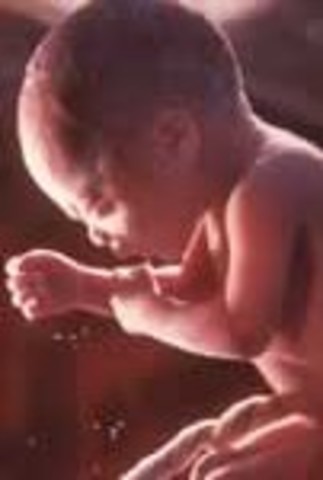

• Week 26 end of second trimester

Week 26 end of second trimester

The baby is more responsive to touch, and the babies muscles become more coordinated and it starts moving around in the womb. The baby has the ability to suck it's thumb which strengthen the jaw muscles, at this time the baby is 14 inches long and weighs around 1.7 pounds.

Fact: you can play with the baby by touching on your stomach